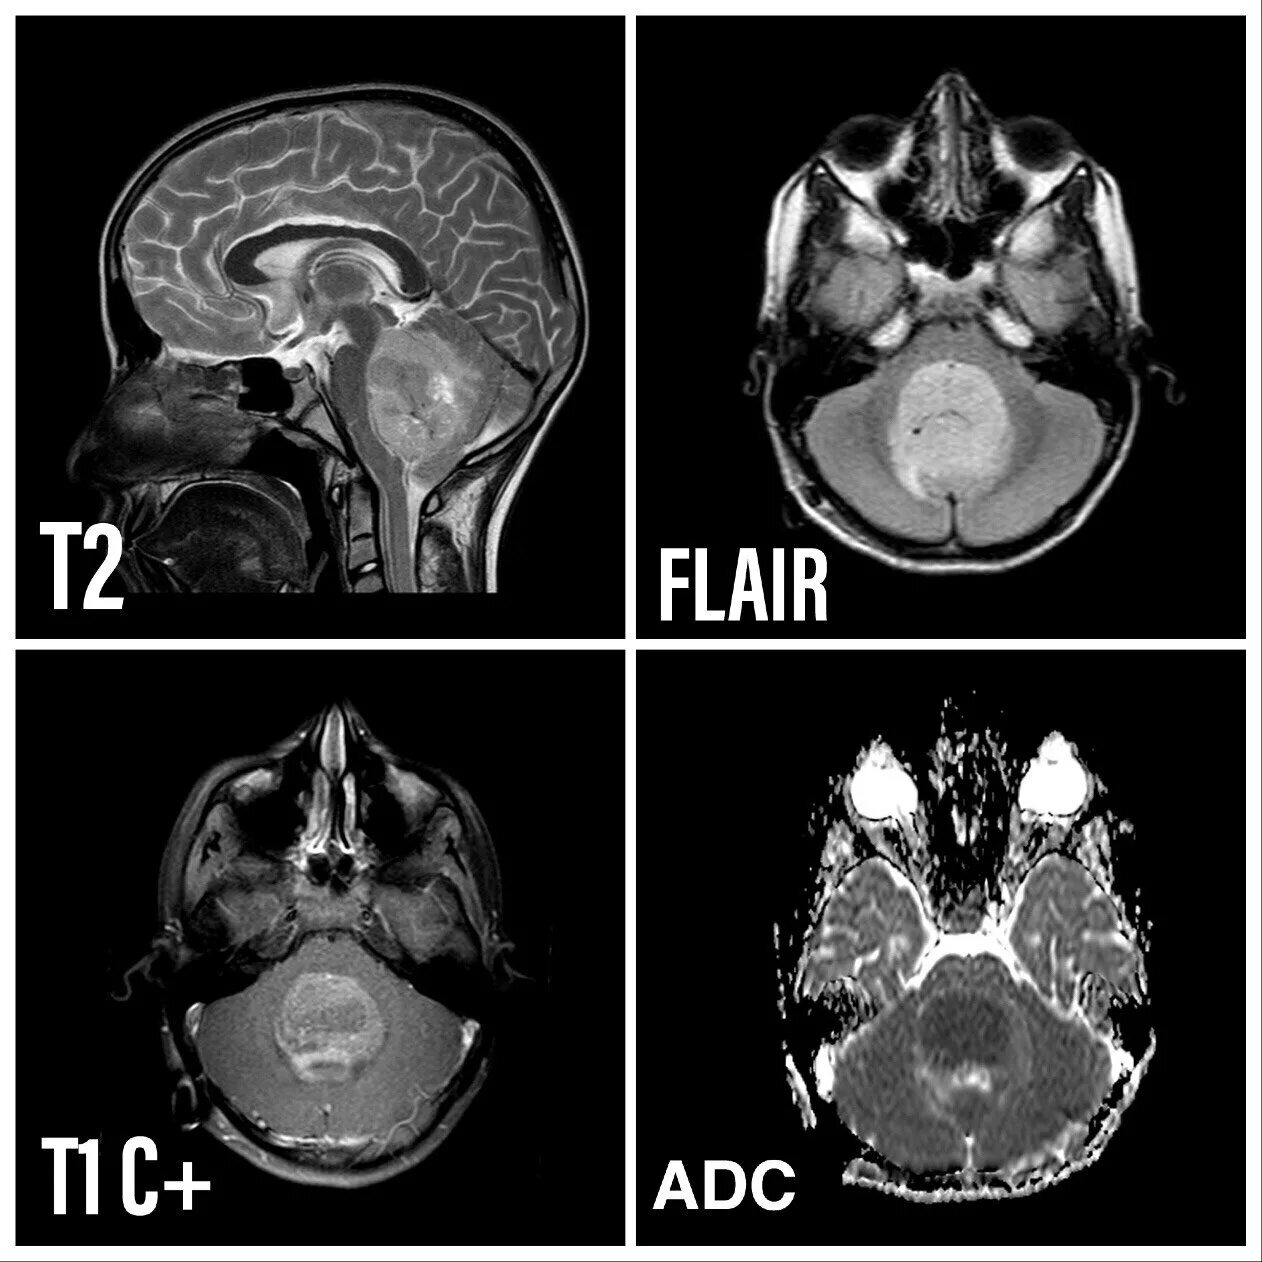

Медуллобластома это